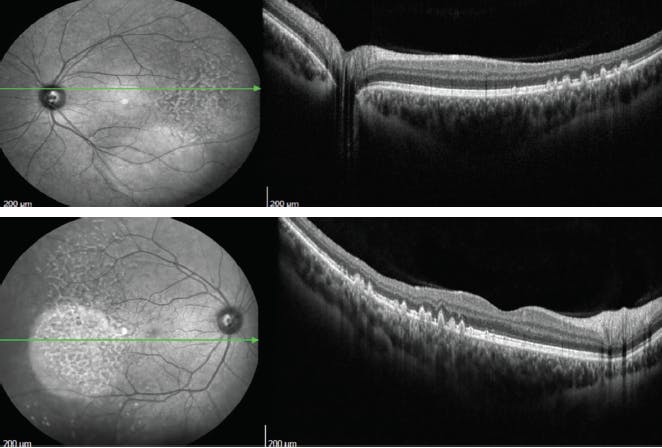

<p>Figures 3 and 4. SD-OCT demonstrated large drusen in the temporal macula bilaterally, with no changes within the retina outside the foveal area.</p>

Figures 3 and 4. SD-OCT demonstrated large drusen in the temporal macula bilaterally, with no changes within the retina outside the foveal area.

Three years after our initial evaluation, OCT remained similar (Figures 5 and 6) and the lesions appeared with hyperautofluorescence (Figure 7 and 8). Four years after the first evaluation, SD-OCT showed the characteristic sawtooth pattern, similar to the findings in the initial exam (Figures 9 and 10). Additionally, on fluorescein angiography, the lesions showed late hyperfluorescence with progressive staining but no diffusion, attesting to the stability of the disease (Figures 11 and 12).

<p>Figures 9 and 10. Four years after initial evaluation, SD-OCT showed a characteristic sawtooth pattern, similar to the findings in the initial exam.</p>

Figures 9 and 10. Four years after initial evaluation, SD-OCT showed a characteristic sawtooth pattern, similar to the findings in the initial exam.